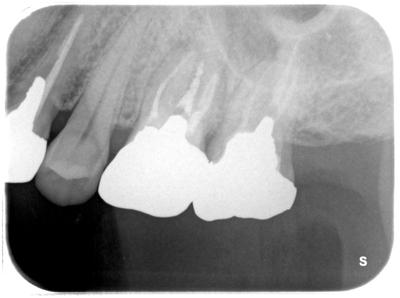

左上67部、他院にて1年程度前に治療したのだが、歯肉にぷくっと何かできては潰れることの繰り返し、噛むと痛い、時々鈍痛、、、、、不安になり当院来院。

根尖に何やら影が、、、、

補綴物を除去してみるとビックリ、、、、、ビタペックス根充。

ビタペックスとは乳歯に用いる薬剤で、通常永久歯には用いない。

おまけにパーフォレーション、クラック、、、、、どのような治療を行っていたのやら。